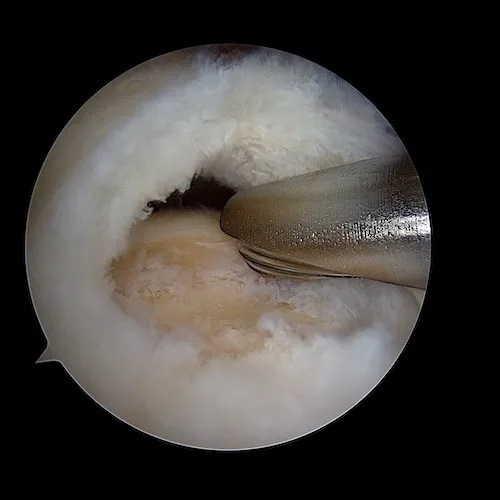

La rupture tendineuse est visualisée dans l'espace bursal sous la forme d'un "trou" dans le tendon. Les fibres tendineuses parthologiques sont réséquées afin de ne garder que du tendon sain. C'est ce tendon qui va être ensuite réinséré sur l'os.

La surface osseuse est ensuite préparée. L'os est avivé grâce à une fraise motorisée. Ce geste permet la revascularisation du tendon réinséré et la cicatrisation sur l'os.